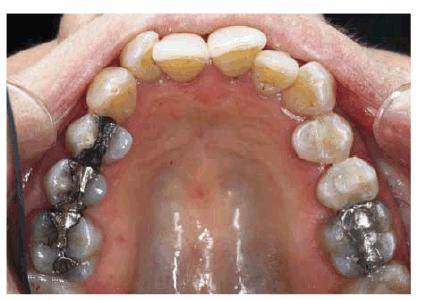

Figure 29-1K: Note the crowding of the mandibular anterior teeth.

Figure 29-1L: The teeth are less crowded, and the new tooth-colored restorations have been placed.

Figure 29-1M: The maxillary arch shows anterior crowding and defective amalgam restorations.

Figure 29-1N: Following 12 months of orthodontic treatment, the patient's amalgam restorations were replaced with posterior composite resin.

Figure 29-1O: Interdisciplinary 949o141j therapy including orthodontics, periodontics, and restorative dentistry combined to produce this attractive result 2 years following the initiation of treatment in this now younger-looking 78-year-old lady.